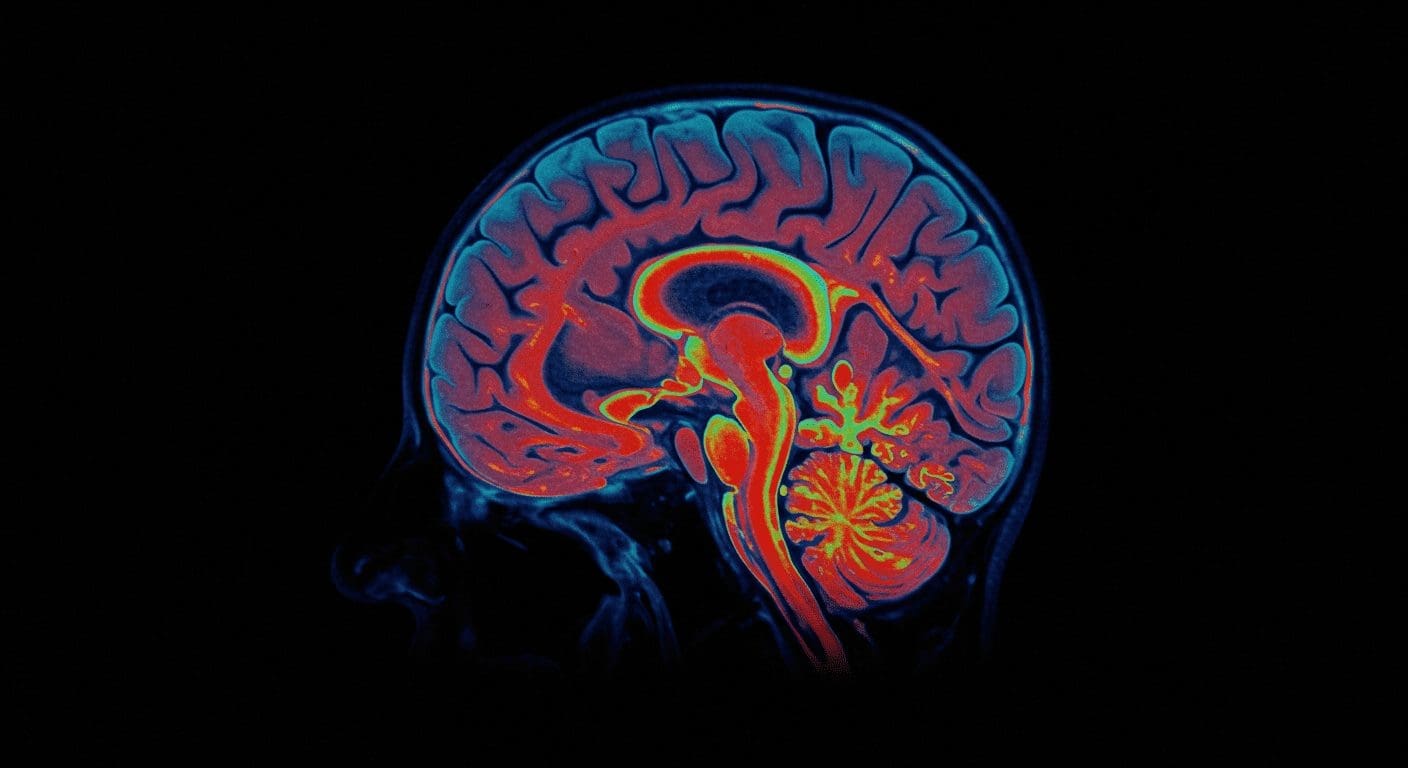

A recent study has revealed that the thalamus, a small but crucial region deep within the brain, significantly influences human conscious perception. Researchers utilized direct intracranial brain recordings to explore the role of high-order thalamic nuclei in this process. Their findings indicate that specific regions within the thalamus act as gateways, transmitting signals to the prefrontal cortex (PFC) and facilitating awareness.

The study involved five patients with chronic headaches who underwent a visual consciousness task while implanted electrodes recorded activity in various brain regions. Using stereoelectroencephalography (sEEG), researchers monitored the intralaminar, medial, and ventral thalamic nuclei alongside the PFC. This approach allowed them to observe neural activity patterns during conscious perception.

Key findings from the research demonstrated that the intralaminar and medial thalamic nuclei exhibited earlier and stronger consciousness-related activity than other regions. Additionally, synchronization between these thalamic areas and the PFC was observed at the onset of conscious perception, highlighting the intralaminar thalamus’s pivotal role in driving PFC activity during this process.

These discoveries expand our understanding beyond the belief that the thalamus facilitates sensory information. Instead, they underscore its active involvement in shaping conscious experiences through interactions with the PFC, offering new insights into the neural mechanisms underlying human consciousness.